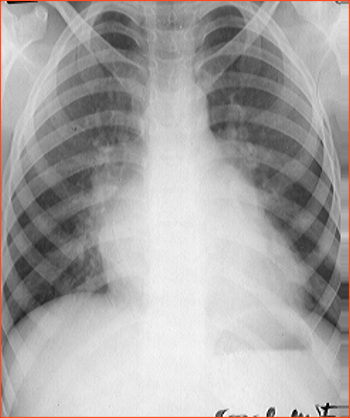

Rx toracică, incidență P-A

DESCRIERE:

pe tot teritoriul pulmonar, bilateral → opacități nodulare multiple de dimensiuni variabile, intensitate medie-mare, omogene, cu contur imprecis delim

confluente

distribuție anarhică

DX: bronhopneumonie

DD:

miliara TBC

MTS pulm hematogene